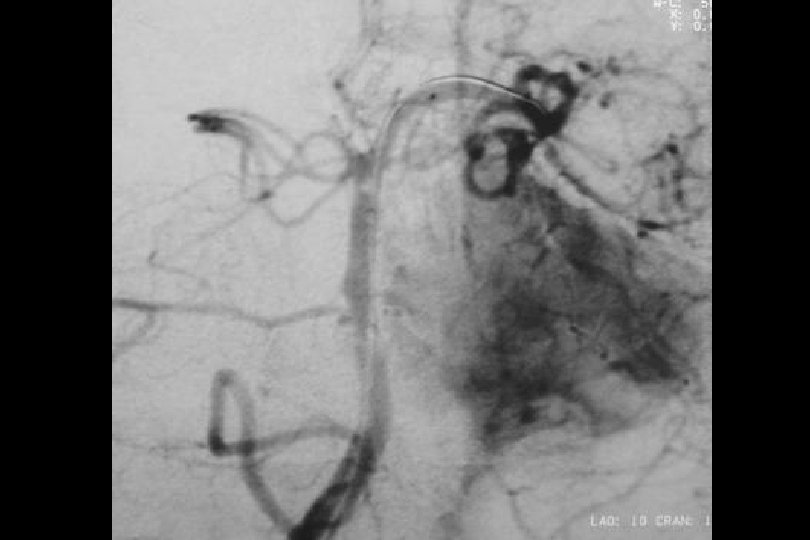

52 y kadın efektiv/test edilmiş ikili antiagregan ted altında iken multipl TIA Basit PTA sonrası

1. Yıl kontrol

1 yıl kontrol PTA Sonrası